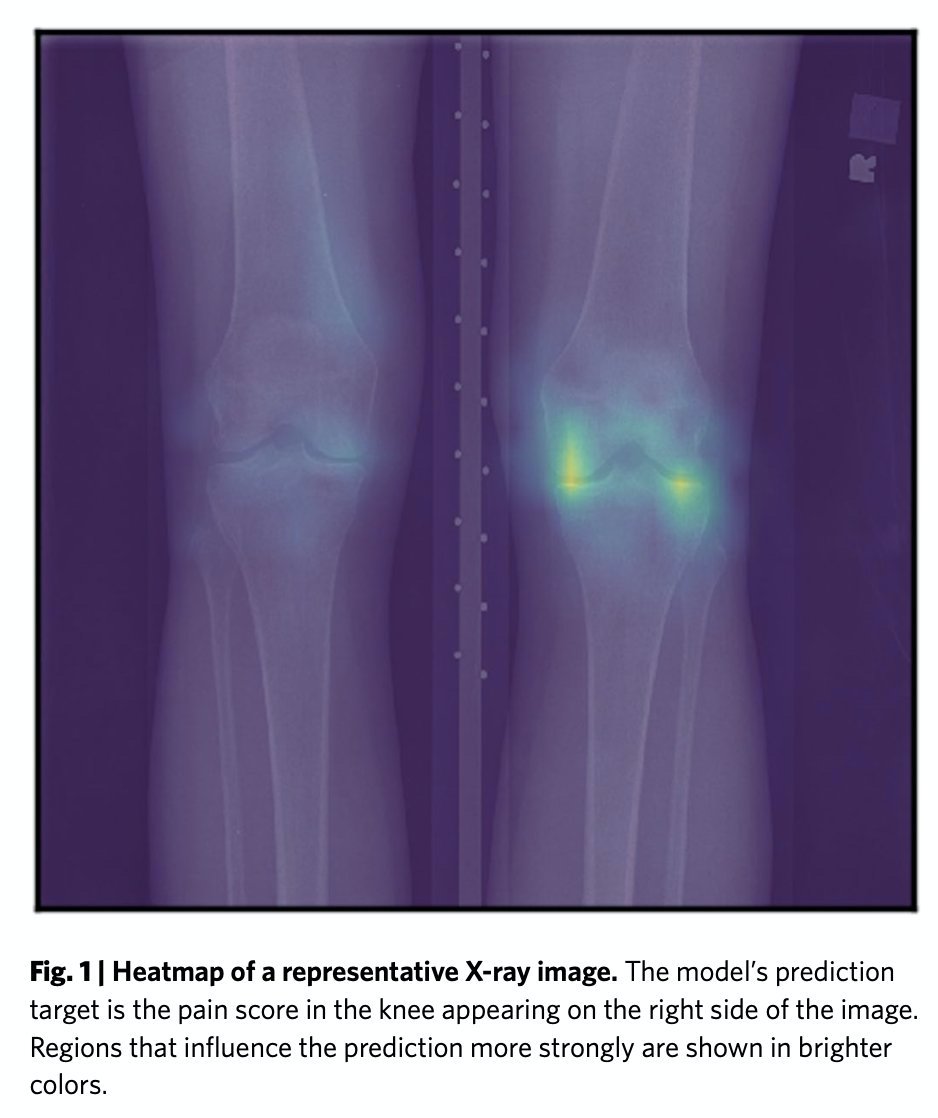

The paper details that an AI algorithm trained to use the patient’s reported pain as the outcome with which to diagnose severity of OA, rather than what the radiologist thought. It was almost *5x better* at EXPLAINING the severity of pain in black patients than radiologists....

The Kellgren and Lawrence grading (KLG) system published in 1952 is used by radiologist across the world to diagnosis the severity of Osteoarthritis (OA). In 1961 is was accepted by the @WHO as the radiological definition of OA for the purpose of epidemiological studies.

The severity of the condition varies from person to person. To help treat OA, the KLG system is used by radiologist as an ‘objective’ way of measuring severity using X-ray scans and determining which treatment patients should receive. Eg a knee replacement or not